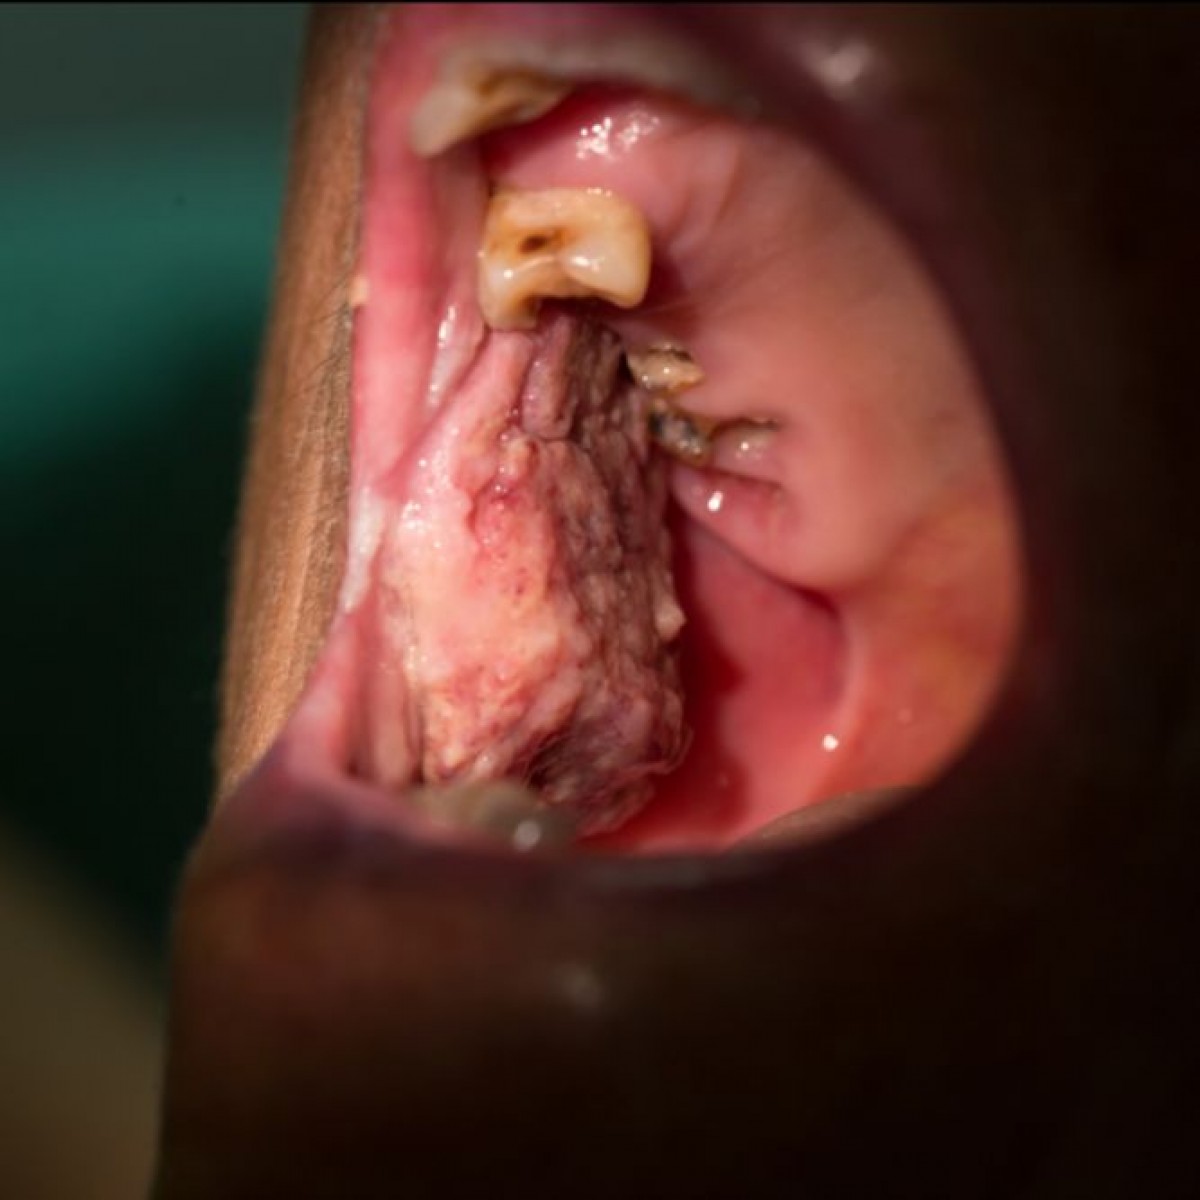

Her intraoral examination revealed multiple pseudomembranous ulcers with erythematous areas and white striae similar to erosive lichen planus. The histological assessment revealed chronic mucositis, while the direct immunofluorescent examination showed negative results, contradicting the diagnosis of both lichen planus and LPP.

Thus, the diagnosis was given as chronic mucositis, and the topical steroid was given. After 6 weeks of steroid application, the lesion resolved. To the best of our knowledge, this is the first report of chronic mucositis in LPP patients. This report could raise the awareness of clinicians to carefully take history as the patient with LPP may suffer from chronic mucositis in the oral cavity as well.